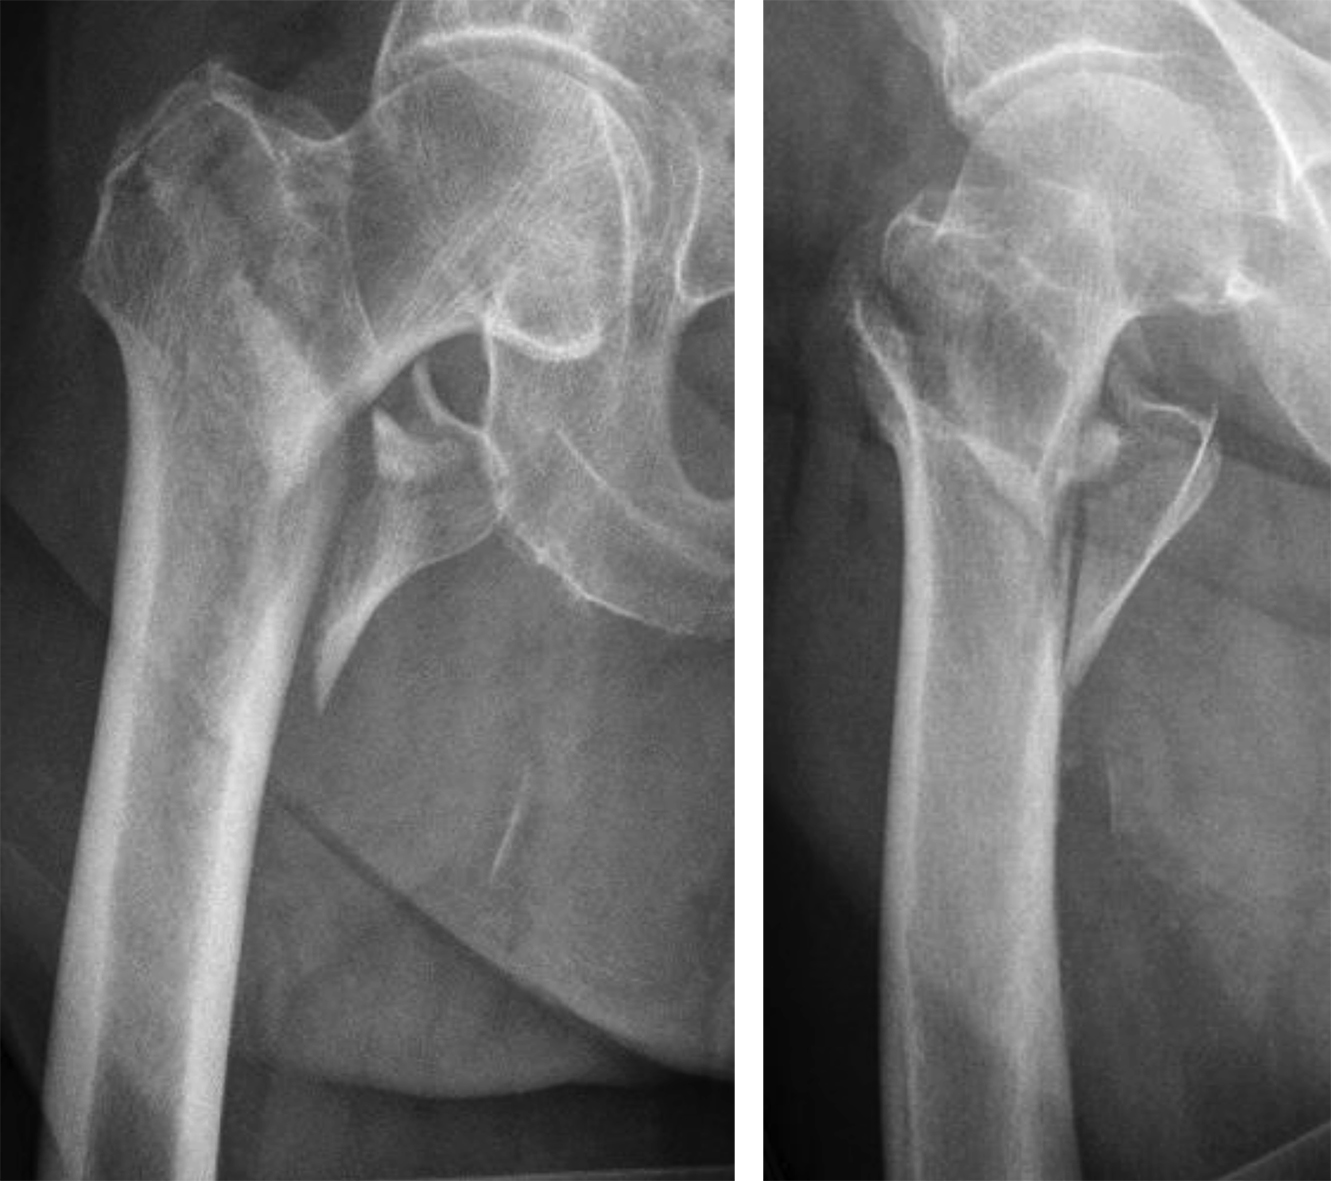

It is widely reported in the literature in Japan that there are many missed unstable femoral trochanteric fracture cases diagnosed only by x-ray, yet CT scans can clearly reveal the unstable fracture pattern.

A 77-year-old man suffered a right femoral trochanteric fracture (Figs 5-8). This case can be diagnosed as AO31-A1. However, the CT shows the detachment of the lesser trochanter (AO31-A2). Precise information of dangerous fracture patterns in advance might simplify the imaging of intraoperative reduction maneuvers and the use of the implants.

In this case, the fracture lines are located in the area of the intended nail insertion point. The 3-D reconstruction images distinctly show that the hollow reamer prevented the fracture fragments from being pushed apart when introducing the hollow reamer close to the fracture line.